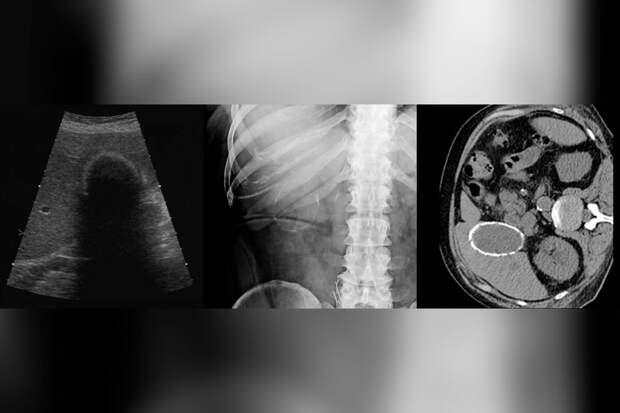

Врачи городской больницы Реутова прооперировали местную жительницу с редкой патологией - "фарфоровым" желчным пузырем. Об этом сообщили в пресс-службе минздрава Московской области.

Женщина обратилась с жалобами на тяжесть в правом подреберье. Ей диагностировали редкую разновидность калькулезного холецистита, когда стенки пузыря покрываются слоем кальция, делая орган твердым.

Пациентке провели малоинвазивную операцию, удалив желчный пузырь через небольшие проколы.

"Сам пузырь настолько затвердел, что его было почти невозможно разрезать скальпелем", - поделились медики.